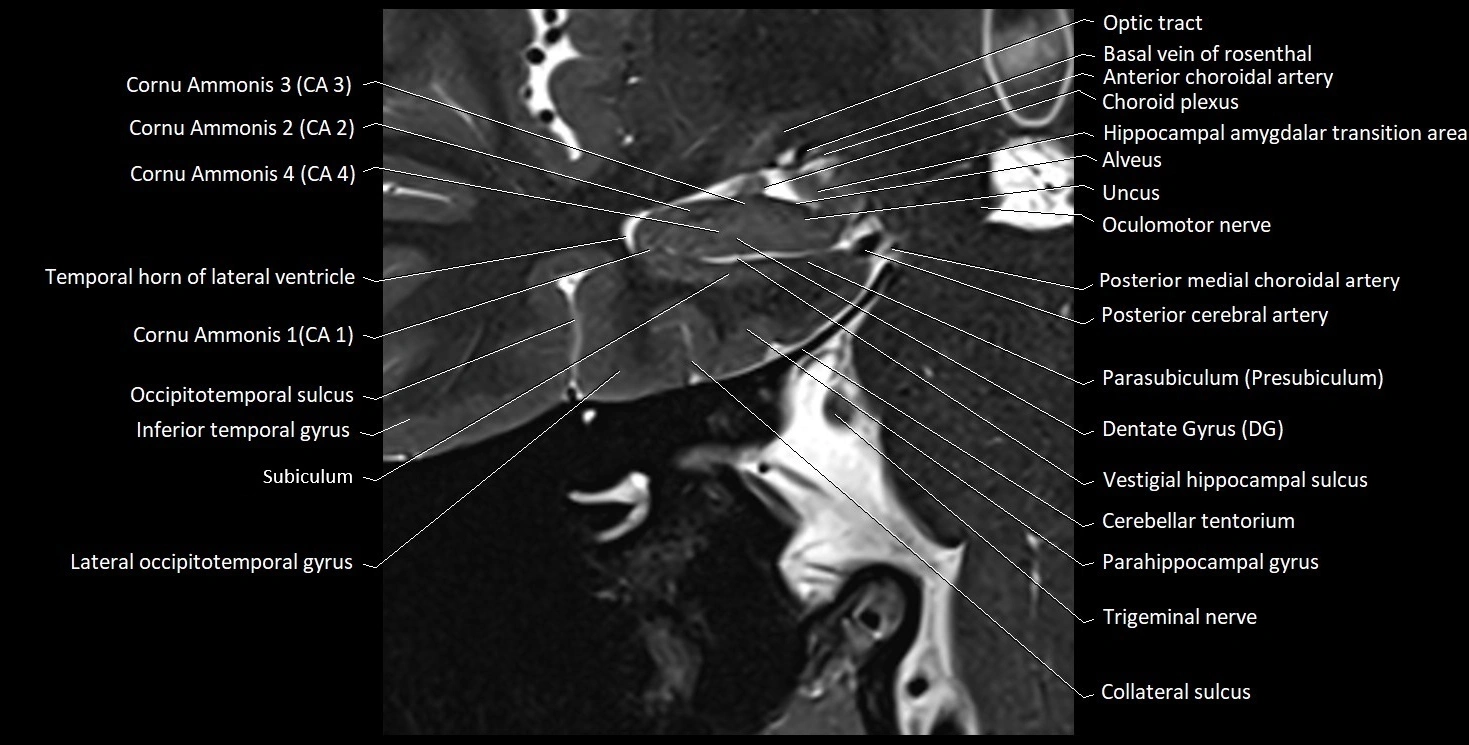

MRI Appearance

T1-weighted images:

• Alveus: Thin linear high signal band (due to myelinated fibers) overlying the hippocampal gray matter.

• Hippocampal gray matter: Intermediate signal intensity.

• CSF of lateral ventricle: Dark (low signal).

• Pathology:

• Sclerosis: Alveus becomes indistinct, with reduced T1 signal and hippocampal atrophy.

• Edema or gliosis: Diffuse hypointensity and blurring of alvear margins.

T2-weighted images:

• Alveus: Low signal line overlying brighter hippocampal gray matter.

• CSF: Bright hyperintense.

• Gliosis or demyelination: Causes increased signal in the alvear region.

• Hippocampal sclerosis: Gray-white differentiation becomes indistinct.

• Edema: Hyperintense change surrounding alveus.

MRI images

image